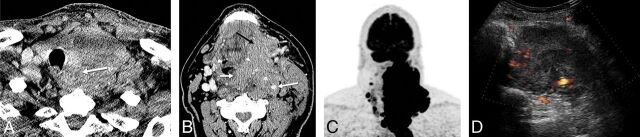

Fig 2.

A 60-year-old man with history of neck pain for 1 month and neck CT demonstrating a large left neck mass biopsied as anaplastic thyroid cancer, stage IVC. A, CECT demonstrates a heterogeneously enhancing solid tumor involving the left thyroid lobe and isthmus, with extension to the tracheoesophageal groove and esophageal invasion (arrow). B, Tumor encases the internal carotid artery (large white arrow), and there is direct extension to the prevertebral space, supraglottis (small white arrow), oropharynx, and floor of mouth (black arrow). C, FDG-PET shows intense radiotracer uptake within the left neck tumor with extension to the mediastinum, and there, nodal metastasis to the right neck. D, Pretreatment sonography with Doppler demonstrates a hypoechoic, solid, diffusely infiltrative mass involving the left lobe with increased vascular flow.